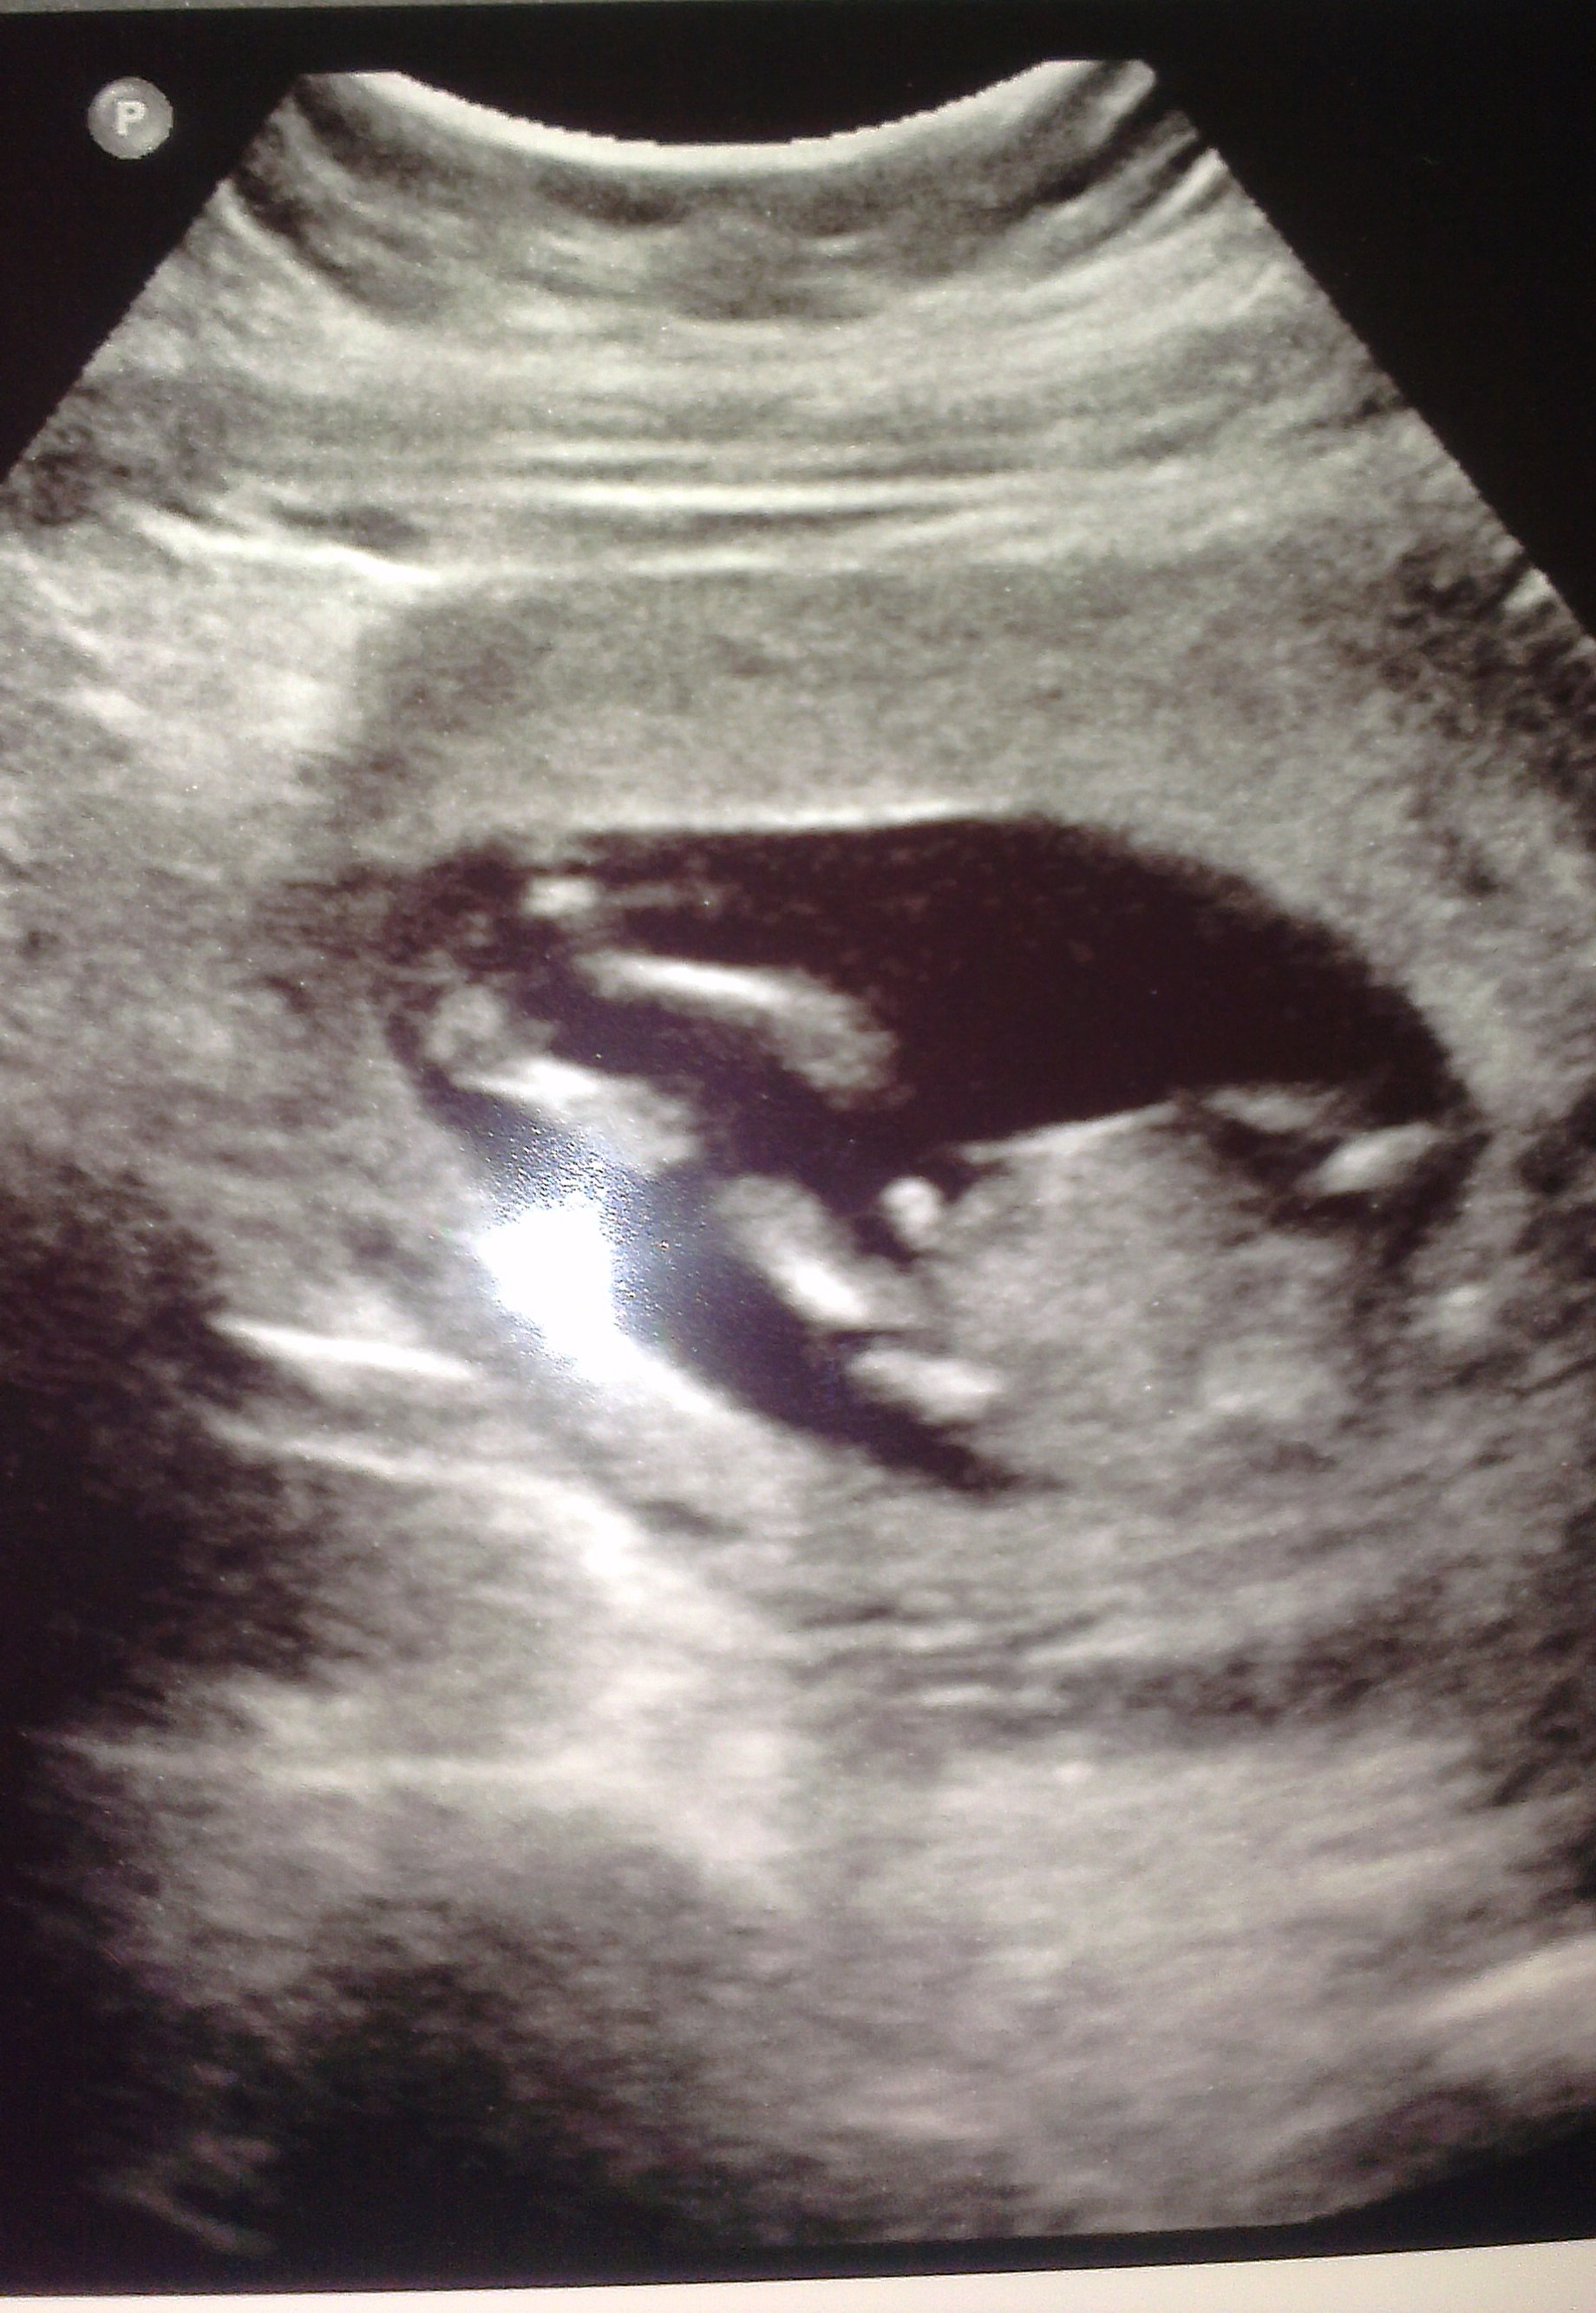

13w 6 day NT scan. Tech said she thought it was a boy. Of course that was before either of these 2 pics. Am I seeing cord or penis here?Thanks in advance!! Attachment 13823 Attachment 13822

The first pic looks like the penis but the second I think is the cord

Thank you all for the responses! I just kept looking at the pics and thinking it could go either way! The first picture is the one I think looks the most penis-y. I'm not really even sure what I'm looking at in the 2nd pic. I assume legs and belly.